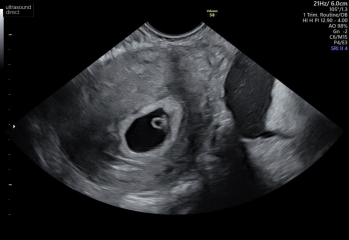

I’ll be honest I was a complete nervous wreck today. I had a internal scan and I couldn’t stop shaking even after we saw the heartbeat but now I feel

so much better X

Keeping everything crossed for baby number three

Cramping and spotting 5 weeks

@TTCournumberthree that’s amazing news I’m so pleased for you! Lovely scan pictures too !!

Oh @TTCournumberthree im so pleased for you!! I had my scan too and saw the little heartbeat fluttering away. I’m 6w so we are so close! X

@bubble55 little june babies! I really went in expecting the worst. It’s such a relief isn’t it x

@bubble55 yes definitely would have shifted any old blood. We were just dumbfounded that it was all ok, so excited though x